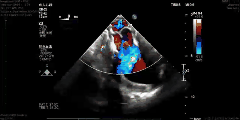

据了解,当天一共完成了4例介入二尖瓣置换产品动物实验,由泰州美凤力动物实验中心创始人、首席科学家魏旭峰亲率团队在活体白猪身上经心尖介入完成二尖瓣置换,手术过程非常顺利,从心尖介入到最后瓣膜释放,仅仅用时两分钟。术后,通过超声对瓣膜功能进行了评价,没有明显瓣周漏,瓣膜活动状态良好,跨瓣压差小,没有瓣膜反流,也没有阻挡左室流出道。又通过直接测压的手段进行了左房压测定,亦无明显升高。术后效果得到了手术团队的高度认可与赞扬。

-术后造影-